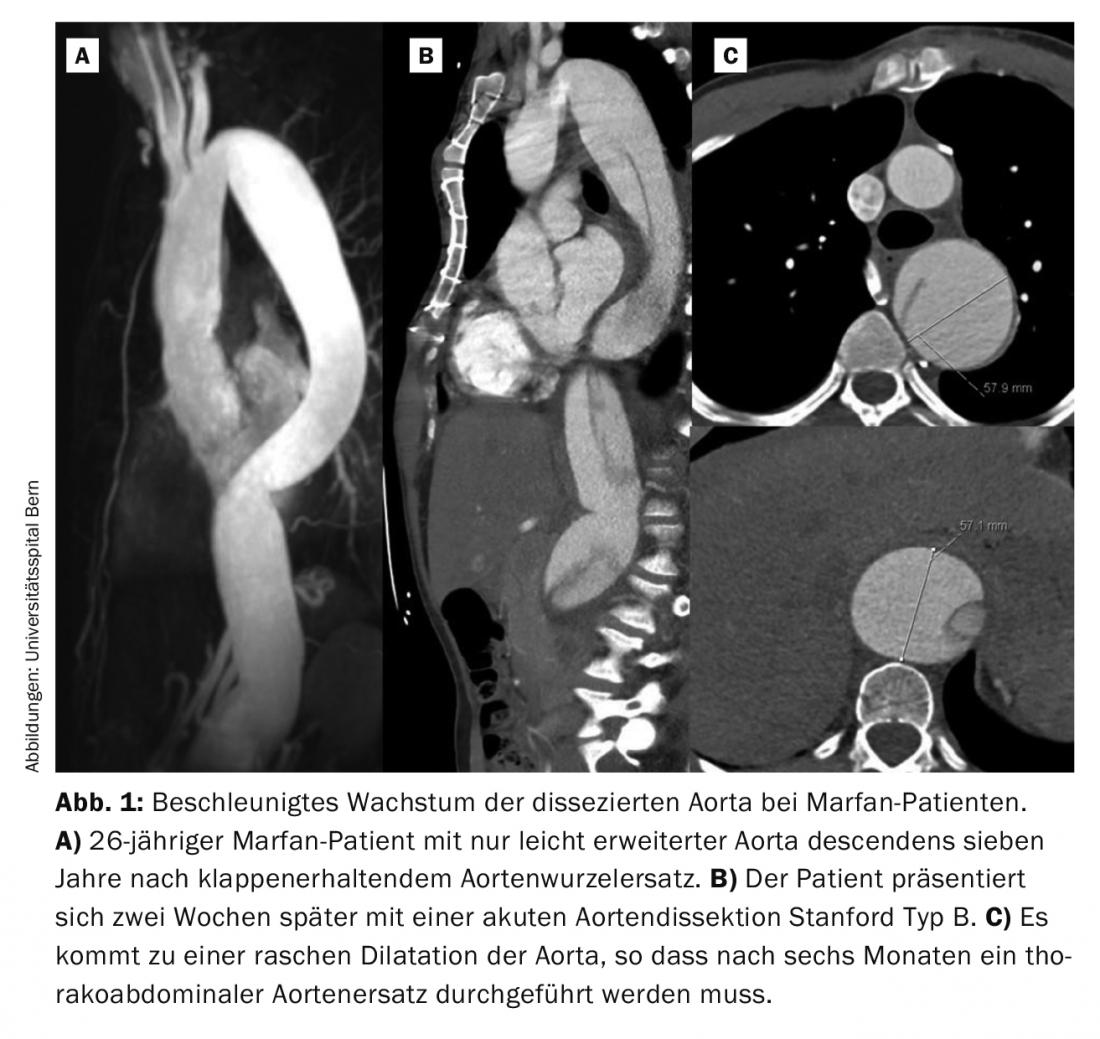

Sin embargo, a menudo la manifestación inicial es una disección aórtica aguda tipo Stanford A o B. En nuestra experiencia de los últimos veinte años, un tercio de los pacientes presentaban una disección aguda. La disección aguda de tipo A es una urgencia quirúrgica y debe tratarse inmediatamente. Incluso con una intervención quirúrgica exitosa, la mitad de estos pacientes requieren una reintervención, sobre todo en la aorta distal, es decir, la no reemplazada. En los pacientes con sustitución electiva de la raíz aórtica, sólo un 10% de los pacientes necesitan repetir la operación. En la mayoría de los casos, se trata de pacientes que han sufrido entretanto una disección aórtica de tipo B. Aunque la disección aórtica de tipo B suele ser inicialmente “no complicada”, es decir, sin malperfusión, en la gran mayoría de los pacientes de Marfan la aorta debe sustituirse posteriormente de forma toracoabdominal. Una característica típica de los pacientes de Marfan es el rápido crecimiento de la aorta disecada en las primeras semanas y unos pocos meses (Fig. 1) . La experiencia demuestra que el 50% de los pacientes requieren cirugía en el primer año tras el suceso [6].